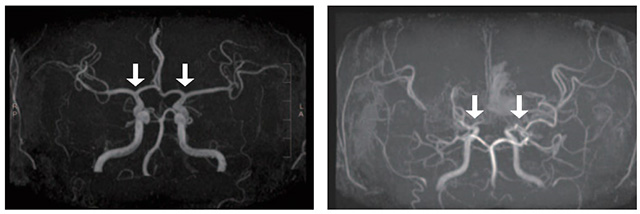

• (왼쪽부터) 정상인 및 모야모야병 환자의 뇌혈관 /사진 제공=서울대병원

▲ (왼쪽부터) 정상인 및 모야모야병 환자의 뇌혈관 /사진 제공=서울대병원